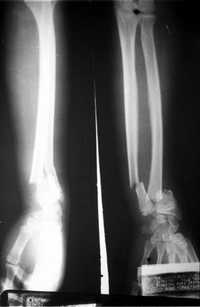

Los implantes de hueso Biograft pueden ser utilizados para atender lesiones de columna vertebral, cadera, rodilla, quistes óseos, etcétera. En tanto, los implantes de tendón permiten sustituir, por ejemplo, el ligamento cruzado anterior de la rodilla.